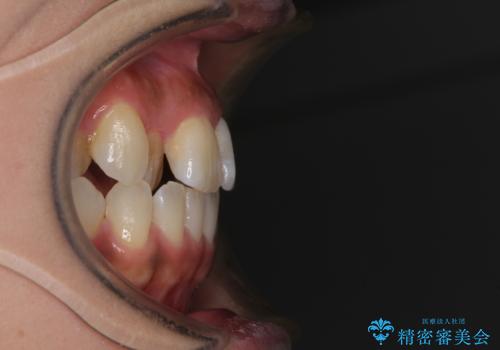

上顎骨の横幅が狭く、歯列が混み合っていたため、急速拡大装置により側方拡大し、咬み合わせと歯列を改善することとしました。

下顎は部分的に咬み合わせに問題があったため、部分的な装置を付けることとしました。

骨格的な問題を解決したことで、下顎は部分矯正で対応することができました。